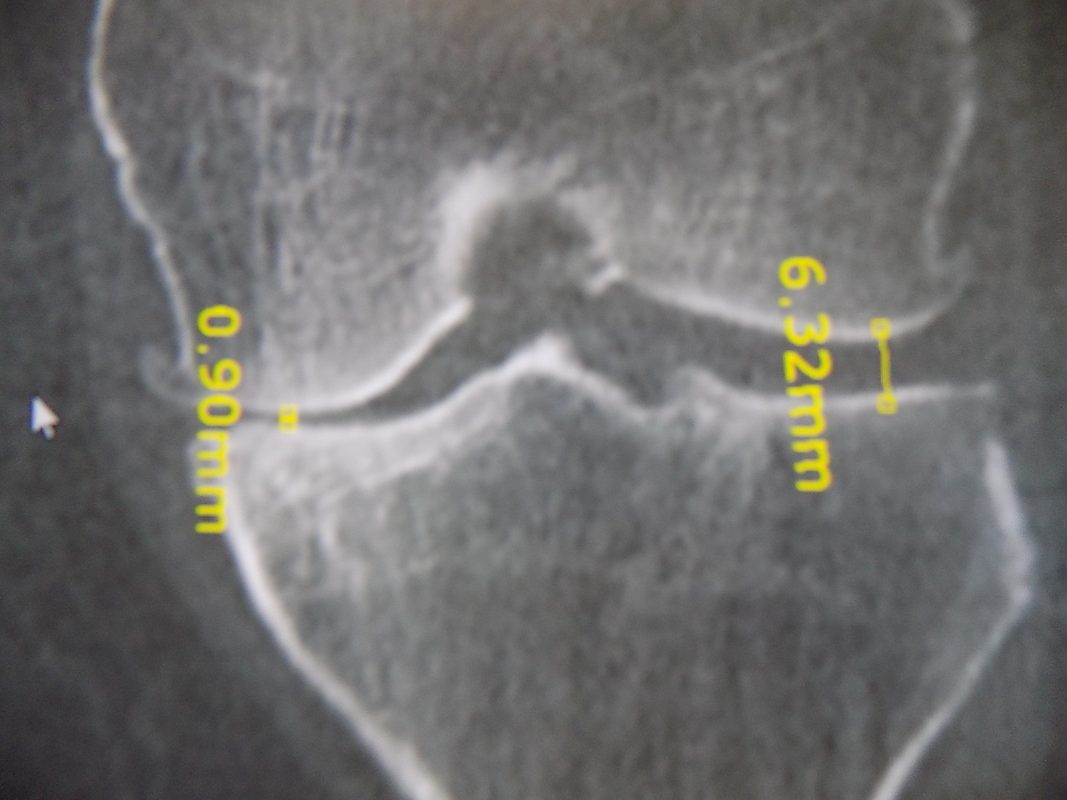

Διάγνωση- Σταδιοποίηση

Διακρίνονται σε 4 στάδια.

Στάδιο Ι. Στένωση του μεσαθριου διαστήματος

Στάδιο ΙΙ. Σκλήρυνση του υποκύμενου χόνδρου

Στάδιο ΙΙΙ. Σκλήρυνση του υπερκείμενου χόνδρου, καταστροφή του υποχόνδρινου οστούν, σχηματισμός οστεόφυτων, οίδημα αρθρώσεως και βραδυνός πόνος

Στάδιο IV. Οστική καθίζηση, καταστροφή μαλακών μορίων μυϊκών ομάδων, υπεξάρθρημα της αρθρώσεως και αλλαγή του μηχανικού άξονα